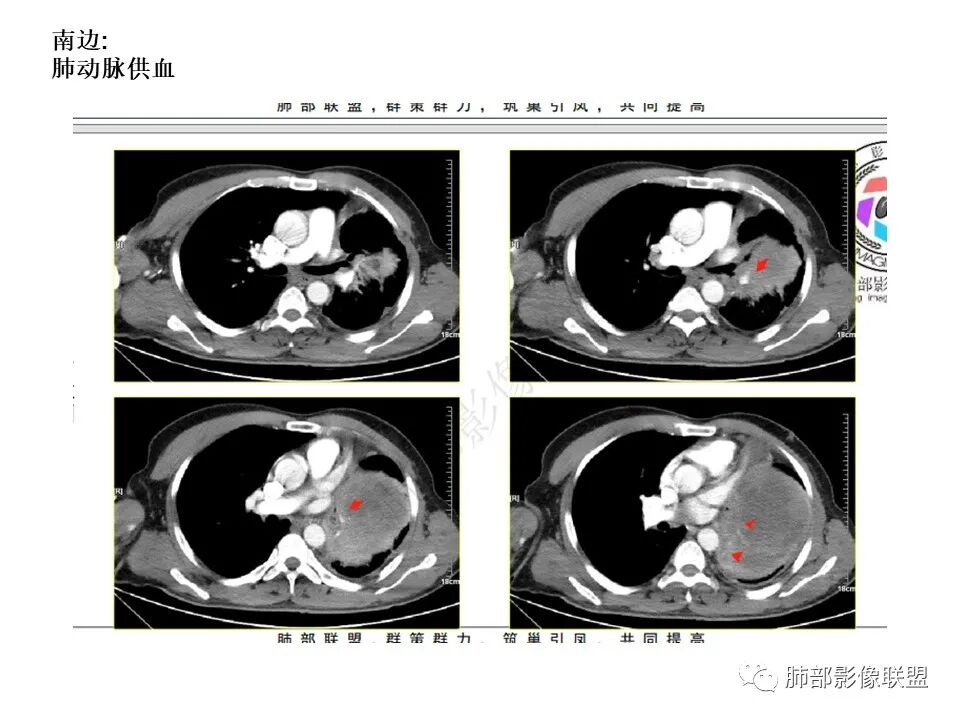

左下肺动脉分支进入肿块,考虑肺内病变。巨大肿块,不均匀强化,较多囊变坏死,少许钙化,考虑恶性肿瘤,以癌肉瘤、肉瘤样癌、肉瘤类、肺母可能

2.左肺巨大块影,上部边界较清楚,占据胸腔大部,对于左肺,“占据”及“推移”兼而有之,左肺上叶支气管推移狭窄,下叶支气管截断。下肺动脉穿行!

3.病灶密度不均,轻度强化,坏死或液化范围甚大,边界可分辨,部分“壁”可见钙化。

巨大占位,包绕下肺动脉,坏死囊变,胸膜疑似侵犯,支气管推移,神纹血管,考虑恶性,大神>肉瘤>sft